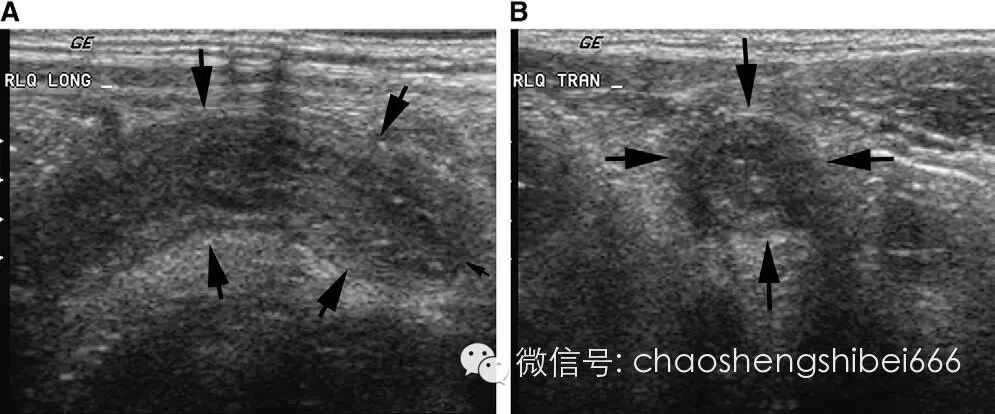

正常的阑尾直径小于等于6mm且有可压缩性(图2),不正常的阑尾通常直径大于等于7mm并且不可压缩(图3)。阑尾是一个管状的盲端,阑尾内的粪石可以也可不显示(图4)。如果阑尾确实存在异常,检查具有可重复性,即移走探头再重复扫查仍然可以找到病变。彩色多普勒超声显示血流增多也可提示存在炎症。在穿孔的病例,可能无法显示阑尾结构,而只见到包块或者脓肿。虽然这些结果不具有特异性,但是由于此种情况下最可能的诊断仍是阑尾炎,所以要考虑阑尾穿孔的可能。

2 11岁女孩的正常阑尾(箭头所示)。阑尾直径4mm,小箭头为阑尾尖端。A长轴图像,B短轴图像。

3 5岁男孩的非穿孔性阑尾炎声像图。长轴(A)和短轴(B)图像均可见肿胀阑尾(箭头),直径12mm。小箭头示阑尾尖端。